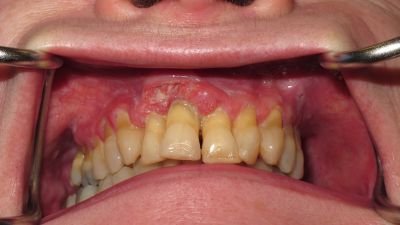

SCC Maxillary Gingivae & Palate

Brown Class 2c

Radial Forearm Flap

No Radiotherapy